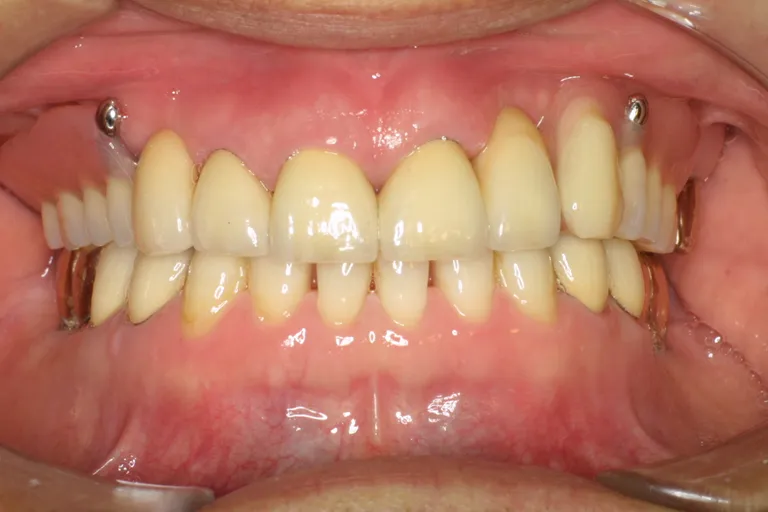

■術後の状態■インプラント・メタルボンド・アタッチメント義歯を含む包括的治療の例です

■術後の状態■

様々な治療法を

用いた

包括的治療の一例